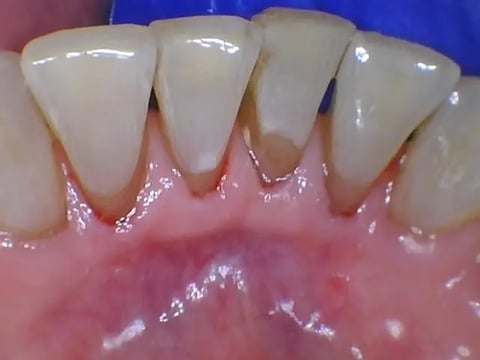

Upon noticing numerous sites of enamel erosion at cervical areas coupled with persistent throat clearing during an appointment, I inquired if my patient had ever been evaluated for silent reflux. He had not but said he was willing to discuss it with his physician during his upcoming annual physical. His chronic throat clearing had become a stressor to him around other people which is not uncommon for those living with silent reflux1, as a recent study elucidated. This discussion led to several assessments including an ambulatory pH test and upper endoscopy where other conditions were ruled out; yet a positive diagnosis of silent reflux while suspected; was not positively confirmed. The patient was started on a proton-pump inhibitor for the next few months, however, the persistent throat clearing did not improve.

(Figure 1. Vulnerable erosion sites on the lingual, Courtesy of Karen Davis)